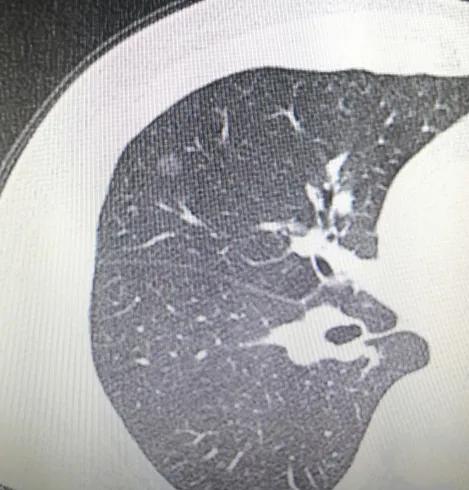

“好日子到头了!!”是今天这位朋友,遇到结节的第一个念头。还是去年,2021年年初体检时,这位患者双肺均发现结节,右肺结节约8mm×7mm,左肺结节约6mm×5mm,体检医生和医生外甥的双重“认证”,直接让这两个结节的“危险程度”上升了一大截。对于疾病的恐惧,对于未来的无力,让他“如坠深渊”。

5月底,这位朋友不远千里来了新桥,带来了所有详细的检查结果,我断定右侧肺结节100%原位,左侧70%原位30%,微浸润;给他仔细分析了具体情况后,建议可继续随访观察,如果心理压力大也可手术。随后的日子里,这位朋友经历检查、等待、再检查,最后决定在2021年年底进行手术。一周时间,顺利出院,手术即治愈,未来不需要再为这个结节烦恼。

2021年1月22日单位体检,第一次做CT发现了左右肺各有一个结节,其中右肺结节约0.8*0.7cm,左肺结节约0.6*0.5cm。当地医生让随访3—6个月。这段时间压力山大,不知道结节性质,也不知道该怎么办。这几天关注了你的贴吧,知道您是除磨大神,劳驾您给看看指点迷津吧。有个电子片,也不知道如何发给您。

2021年1月22日体检首次发现左右肺各有一个璃结节,分别是0.6*0.5cm和0.8*0.7cm,2月14日晚贴吧上您说三个月复查再精准施策。4月17日在当地做了薄层CT,纠结了三个多月了,劳驾您费心再给看看吧,确定一下结节的性质,应该如何处理。前两张是1月22日的片子,后面是4月17日的片子。期待您百忙之中给看看,万分感谢!

左侧的微,右侧的原位。可手术,也可以再随访一段时间看看。

右侧结节介于非典型增生到原位之间,非常安全,安心随访。左侧结节,微或原位腺癌,已经前者可能性更大了,楔形切除小手术即可根治。